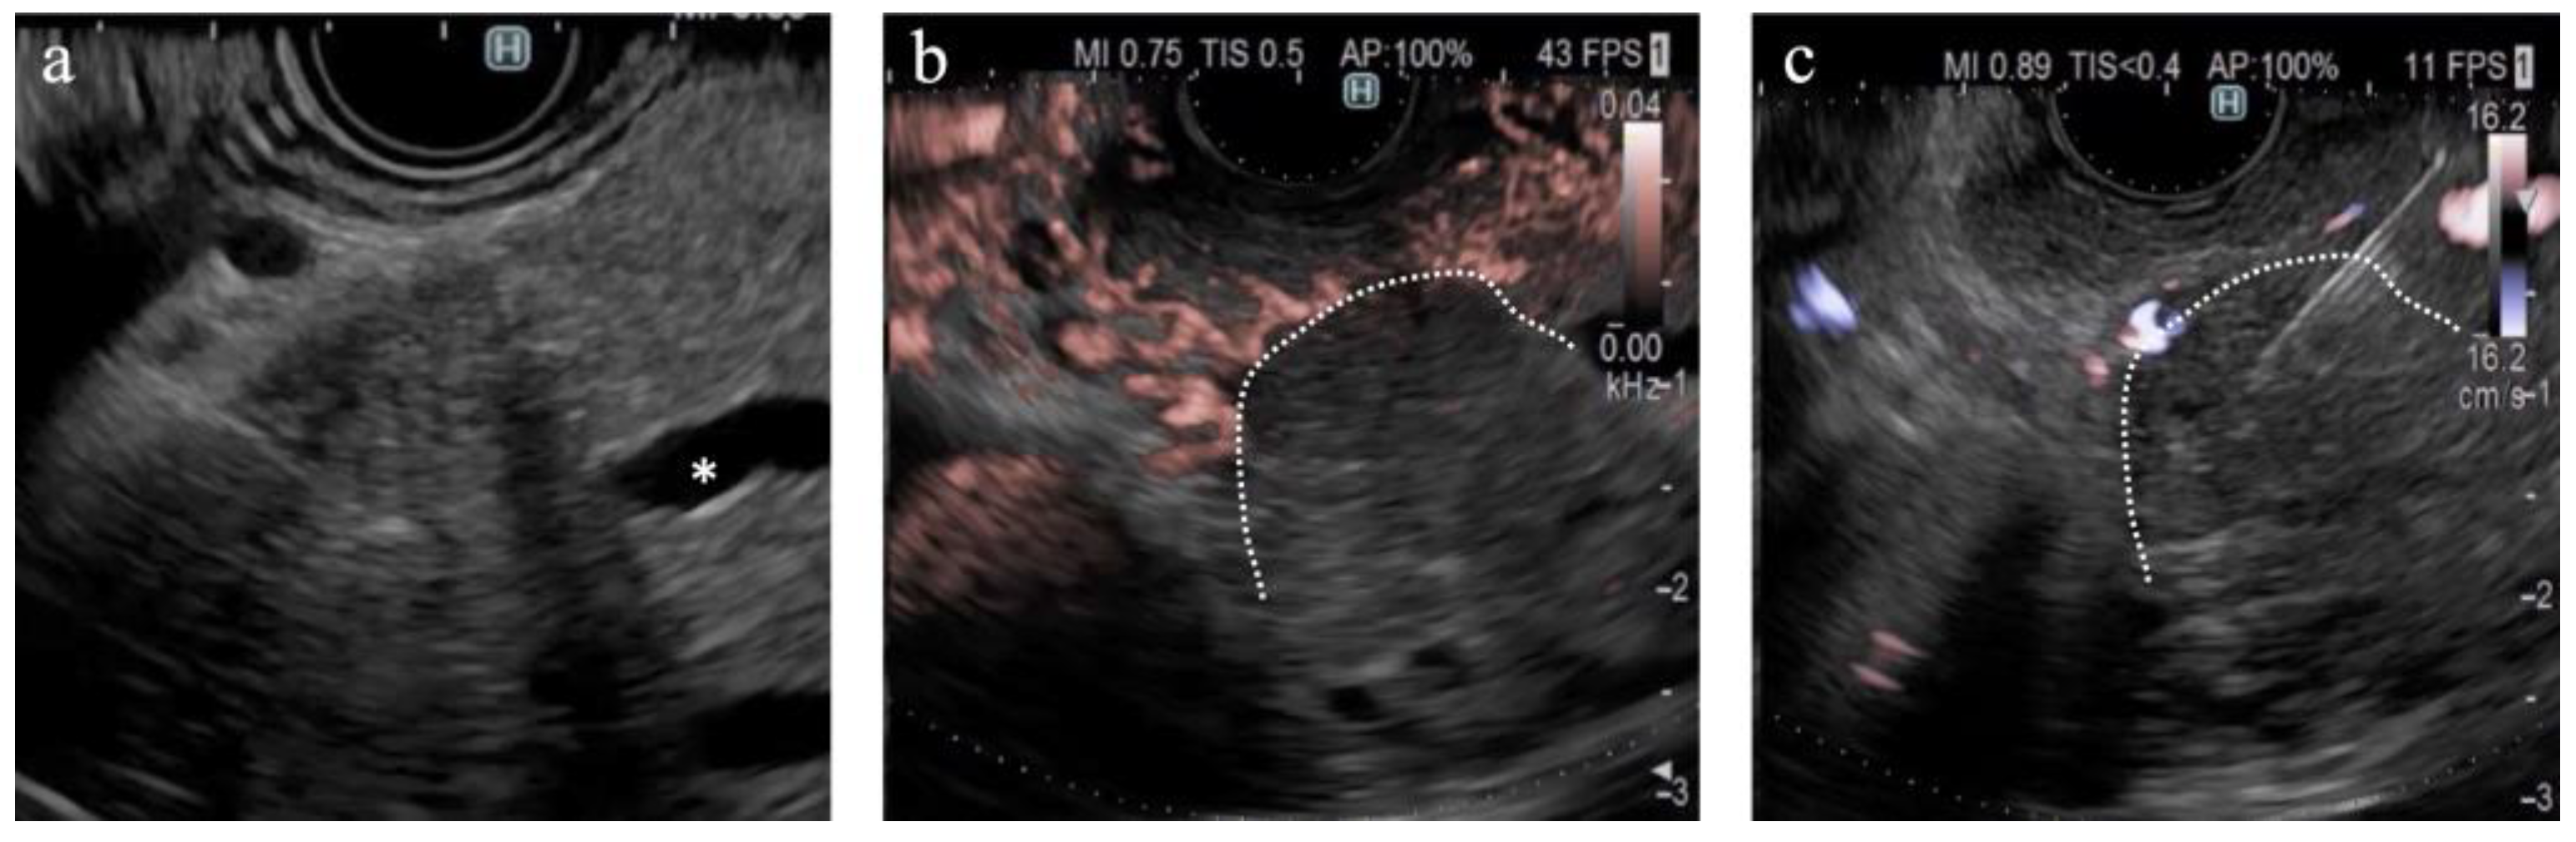

Figure 5.

A case of pancreatic cancer. (a) On B-mode, the main pancreatic duct is obstructed in the pancreatic head (*); however, the tumor margin is unclear. (b) On DFI, the tumor margin is detectable because of the interruption of vessels in the pancreatic parenchyma. (c) Endoscopic ultrasound-guided tissue acquisition was successfully performed according to the margin on DFI.